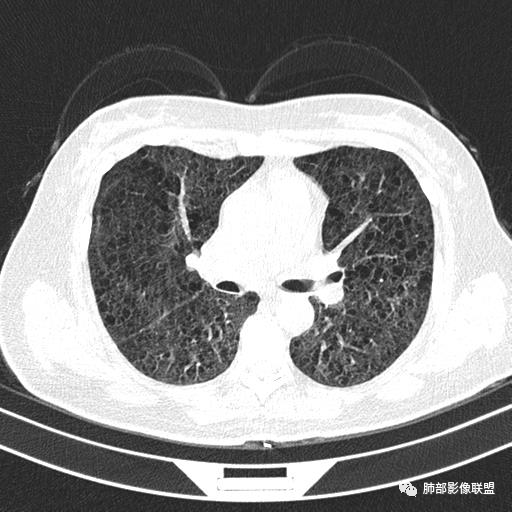

中年女性育龄期妇女,咳嗽气喘,无吸烟史,有苯吸入史。影像:双肺弥漫均匀小囊腔,无明显分布优势,囊腔形态欠规则,壁薄,部分囊腔边缘血管征,伴双肺弥漫磨玻璃影,无结节,考虑lam,鉴别苯中毒肺损伤,囊腔多有分布优势,小叶中心分布为主,形态规整等

女,46,活动性气喘1年。苯吸入史半年。胸部CT:两肺弥漫囊腔,上至肺尖,下至肋膈角,形态类似小囊腔。考虑:LAM,鉴别LIP,BHD,PLCH等。

双肺多发大小相近的囊状影,分布趋势趋于一致,中年女性,考虑LAM。部分囊内见血管及分隔影,小叶中心性肺气肿代排

CT表现:双肺弥漫大小不等的薄壁囊腔,囊壁<2mm,外形规则,血管影多位于囊腔周围,囊腔之间肺组织正常,随着疾病进展到晚期,囊腔变大、增多,不可胜数,囊腔可融合成较大的囊,与肺气肿相似,形成间质性肺纤维化。部分病例可出现结节影。

1.小叶中心性肺气肿:上肺为主,无壁,中央见小血管影,位于小叶核心周围,部分血管可推移到边缘,周围肺组织正常